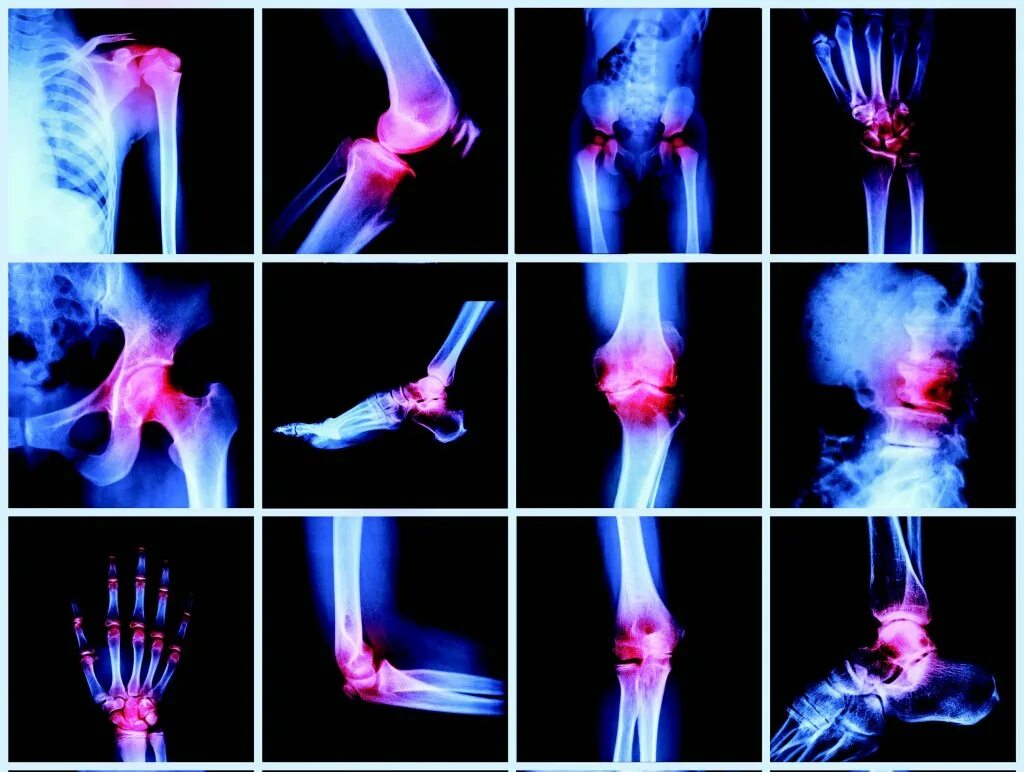

Ревматология артрит